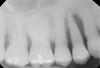

The clinician also must consider the status of the adjacent teeth. Figure 6 shows teeth Nos. 29 and 31 prepared for a fixed bridge. Factors to be considered in this example were the short root of tooth No. 29 with a distal biologic width violation and a short root trunk on tooth No. 31 (which leads to furcation involvement with a small amount of facial or lingual bone loss). This patient also had periodontal disease, which further decreased the long-term prognosis of the fixed bridge option. No prospective studies directly compare the longevity of the two options: a three-unit fixed bridge vs an implant.37 Other factors that complicate comparisons of an implant vs a fixed three-unit bridge are the variability of fixed bridges as well as the variability of the implants (amount of bone, implant length, etc). For example, endodontically treated abutment teeth do not last as long as nonendodontically treated abutment teeth.38 Restorations on teeth with endodontic posts and a minimal length of ferrule do not persist as long as those on teeth without a post and at least a 2-mm ferrule.39

Figure 6   Tooth No. 29 with the temporary build-up close to the osseous crest. Tooth No. 29 has a short post, and tooth No. 31 has a very short root trunk.

Figure 6

Figure 7  Condition of the teeth seen in Figure 6, approximately 5 years after restoration. Note the extensive furcation involvement of tooth No. 31 and its residual periapical radiolucency.

Figure 7